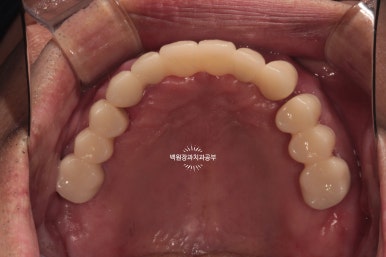

그리고 임시치아를 붙여드렸습니다.

사실 임시치아라 치아 모양도 둥글둥글하고 색깔도 예쁘지 않습니다.

그리고 임시 치아 사이에 간격도 존재하구요.

최종 보철물.. 드디어 제작이 되었습니다.

사실 정말 정말 감동적인 순간입니다... 우리 환자분께서 이 날만을 얼마나 기다리셨을까요.....

전체 임플란트를 완성하는데 전체 치료기간은 약 8개월 정도 걸렸습니다. 상당히 빨리 졸업하신 편이에요!

정면에서 보시면 임시 치아와 다르게 훨씬 깊이감 있는 색상으로 제작되어 자연스럽고, 완성도 있는 형태를 확인하실 수 있습니다.

그리고 치과용 파노라마로 확인해보시면, 정확한 위치에 정확한 보철물이 제작되어 상당히 조화로운 결과를 확인하실 수 있으실거에요! 치과의사로 살면서 가장 기쁘고 감동적인 순간 중 하나입니다.

정말 너무너무 보람찹니다 :) ㅎㅎ 환자분께서도 굉장히 만족해하셨어요!